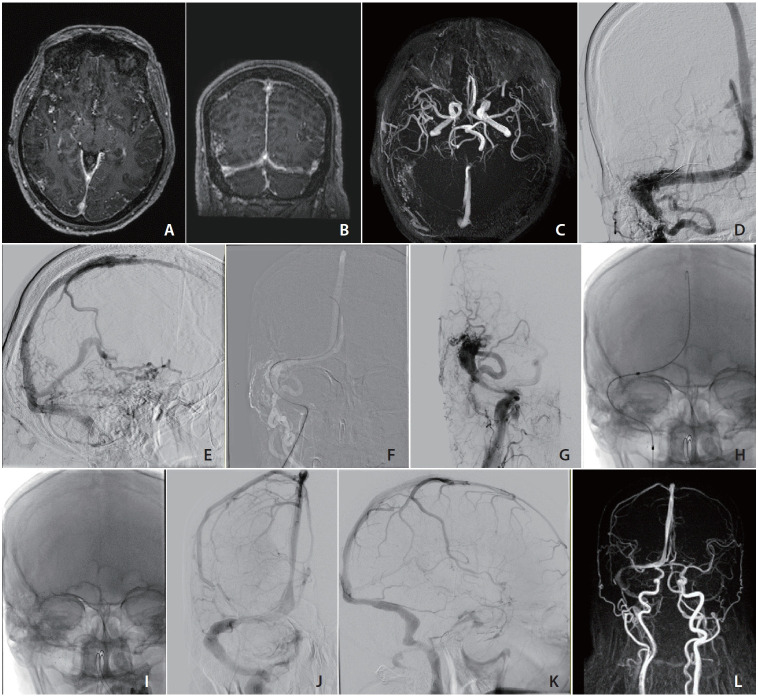

硬脑膜动静脉瘘是一种罕见的血管畸形,常并发窦血栓和皮质反流。我们报告一例右侧横窦出现Cognard型IIb型dAVF并伴有同侧乙状窦血栓形成的患者,由于对侧窦发育不全,不适合常规栓塞。一种新的治疗方法包括直接颈静脉穿刺、静脉再通和使用0.035英寸硬导丝支架植入术,有效地将dAVF降至Cognard i型。在3个月的随访中,血管造影结果稳定,临床明显改善,无癫痫发作,证实了窦内支架植入术作为一种独立治疗在解剖学上具有挑战性的病例中的有效性。

Dural arteriovenous fistulas (dAVFs) are rare vascular malformations, often complicated by sinus thrombosis and cortical reflux. We report a patient with a Cognard Type IIb dAVF at the right transverse sinus and ipsilateral sigmoid sinus thrombosis, unsuitable for conventional embolization due to contralateral sinus hypoplasia. A novel therapeutic approach involving direct jugular vein puncture, venous recanalization, and stenting using a stiff 0.035-inch guidewire effectively downgraded the dAVF to Cognard Type I. At 3-month follow-up, stable angiographic outcomes, marked clinical improvement, and absence of seizures confirmed the efficacy of sinus stenting as a standalone treatment in an anatomically challenging case.